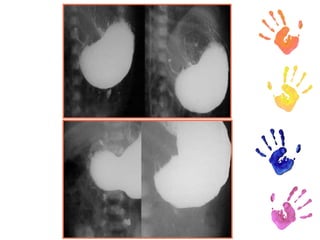

Diagnóstico. RX  “Signo de la cuerda” Ecografía: del píloro mayor de 4mm o una longitud pilórica global mayor de 14 mm.  Estudios baritados.